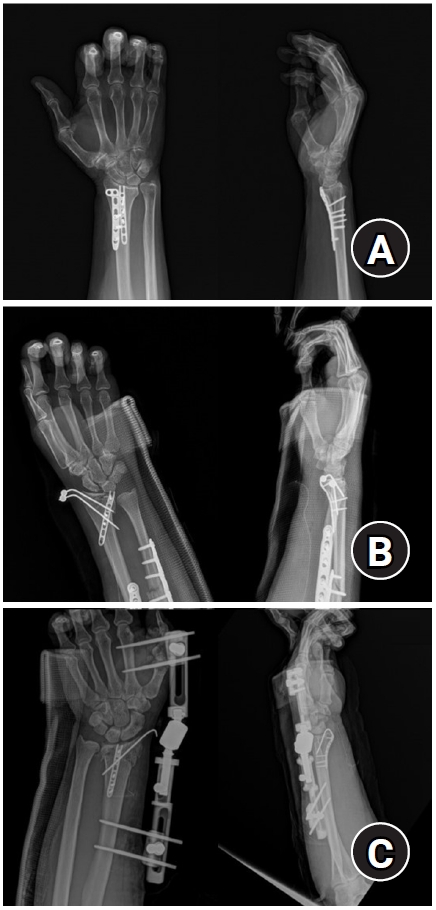

Fig. 3.

Postoperative radiographs (anteroposterior and lateral). (A) Volar articular marginal fragment of the distal radius fixed by two plates: a standard 2.4 mm LCP-L distal radius plate (Synthes) and a 2.0 mm locking compression plate distal ulnar hook plate (Synthes). (B) Additional percutaneous pinning after plating. (C) Additional percutaneous pinning and external fixator after plating.

jmt-2025-00241f3.jpg